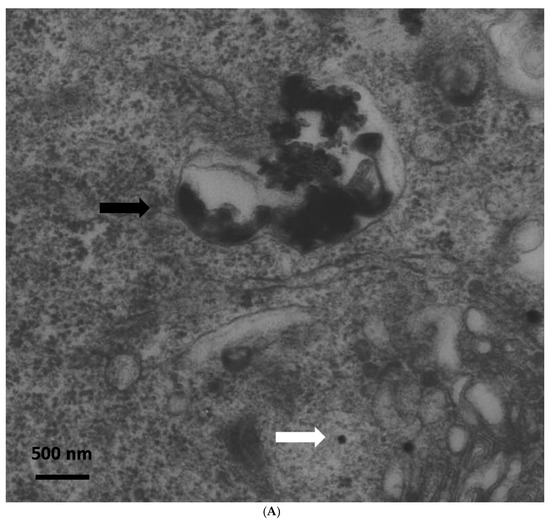

Immediately after exposure, no ZnO-NPs were detectable within the cells. Particle aggregates were found attached to the cell membrane, however, no inclusion of particles into the cells was observed. Clearly, the intracellular presence of ZnO-NPs within the exposed ASCs could be determined at all other time points (one, two, three, and four weeks after exposure). After one week, TEM patterns still showed some intracellular vesicles in the cytoplasm containing small zinc oxide particles in the exposed ASCs (Figure 1). After two weeks and at later time points, no more particle-containing vesicles were found. Instead, free particle aggregates were seen in the cytoplasm or rarely in organelles, but preferably lysosomes (Figure 1B). No inclusion into the nucleus was assessed.

(A) Transmission electron microscopy (TEM) photograph of intracellular distribution of zinc oxide nanoparticles (ZnO-NPS) in human adipose tissue-derived stromal cells (ASCs) one week after 24 h of exposure. The black arrow indicates a vesicle containing conglomerates of ZnO-NPs. The white arrow indicates single particles in the cytoplasm (scale bar represents 500 nm). (B) TEM photograph of agglomerated ZnO-NPs within a lysosome (indicated by the white arrow) in human ASCs, two weeks after exposure. The scale bar represents 500 nm.